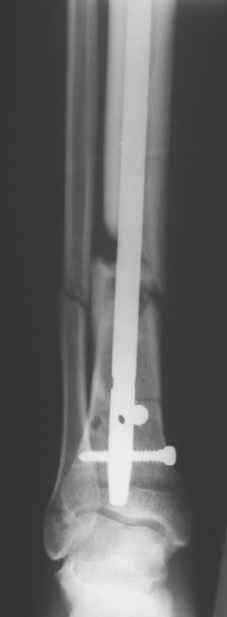

Сегодня прооперировали без открывания. Хотел-бы услышать комментарии по поводу послеоперационной нагрузки.